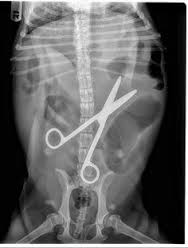

Screws. You heard right. Small, about 1 cm, screws that I had removed from a massage table that I was repairing. They looked a little like this: